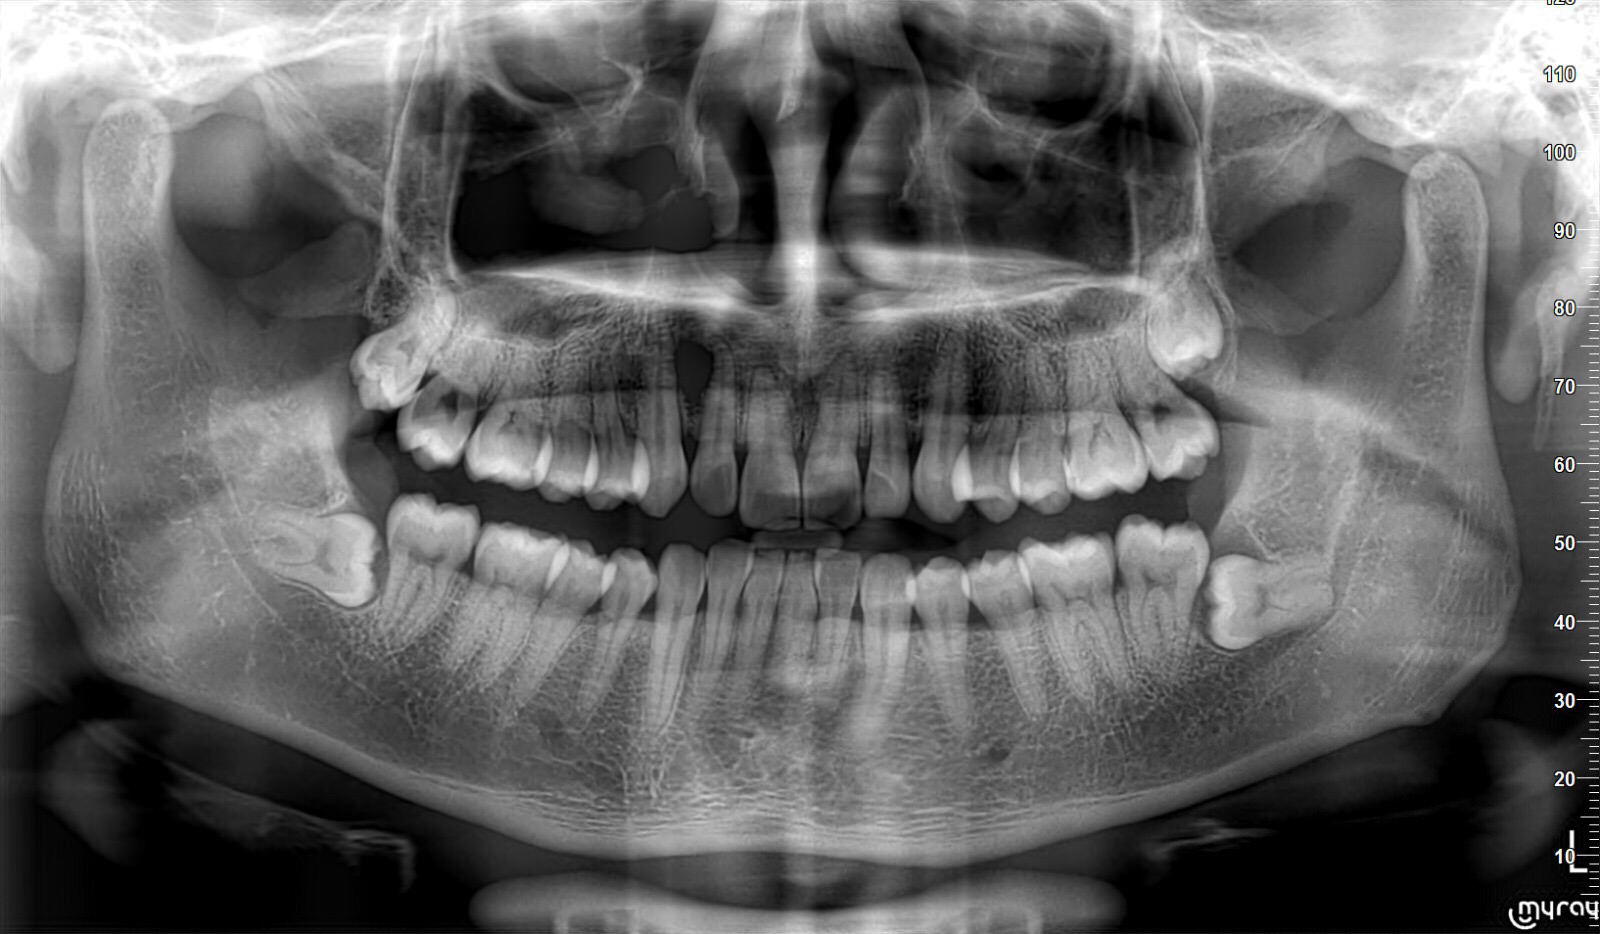

chingwong • • 34257 次浏览今天去看牙医,拍了X-Ray,但是Dentist说他们拔不了我的智齿,因为长得位置不对,拔完可能伤害神经,导致脸部麻木,让我去医院拔。不知道有没有类似经历的狮城帮儿?附图一张,最下面左右两颗横着长的是智齿。

牙医说他们拔不了我的智齿今天去看牙医,拍了X-Ray,但是Dentist说他们拔不了我的智齿,因为长得位置不对,拔完可能伤害神经,导致脸部麻木,让我去医院拔。不知道有没有类似经历的狮城帮儿?附图一张,最下面左右两颗横着长的是智齿。